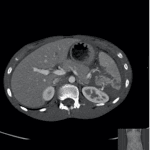

Ultrasound scanning of the appendix

Appendicitis is one of the most common causes of acute abdominal pain in both children and adults, and remains the most frequent abdominal surgical emergency globally, with approximately 50,000 acute appendicectomies performed annually in the UK. Timely diagnosis is key for optimising outcomes with appropriate treatment. Delays in diagnosis and initiation of treatment can lead […]